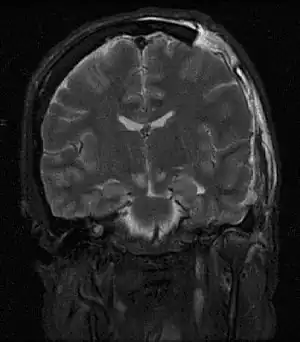

| MRI showing injury due to brain herniation | |

Brain herniation is a potentially deadly side effect of very high pressure within the skull that occurs when a part of the brain is squeezed across structures within the skull. The brain can shift across such structures as the falx cerebri, the tentorium cerebelli, and even through the foramen magnum (the hole in the base of the skull through which the spinal cord connects with the brain). Herniation can be caused by a number of factors that cause a mass effect and increase intracranial pressure (ICP): these include traumatic brain injury, intracranial hemorrhage, or brain tumor.[1]

Treatment involves removal of the etiologic mass and decompressive craniectomy. Brain herniation can cause severe disability or death. In fact, when herniation is visible on a CT scan, the prognosis for a meaningful recovery of neurological function is poor.[2] The patient may become paralyzed on the same side as the lesion causing the pressure, or damage to parts of the brain caused by herniation may cause paralysis on the side opposite the lesion.[11] Damage to the midbrain, which contains the reticular activating network which regulates consciousness, will result in coma.[11] Damage to the cardio-respiratory centers in the medulla oblongata will cause respiratory arrest and (secondarily) cardiac arrest.[11] Investigation is underway regarding the use of neuroprotective agents during the prolonged post-traumatic period of brain hypersensitivity associated with the syndrome.[17]